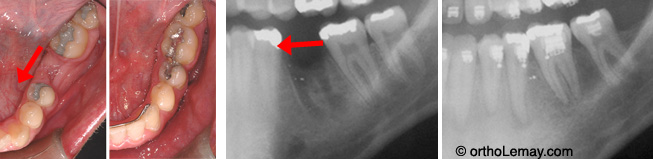

Fermeture d’un espace d’extraction de 11 mm ce qui évite de faire remplacer une molaire par un pont ou un implant.

Fermeture d’espaces (1)

Mini-vis d’ancrage inférieure et ressort utilisés pour fermer un espace. Ces vis sont conçues spécifiquement pour l’orthodontie et ont des formes spéciales pour y attacher des ressorts. Dans cet exemple, le but est d’avancer les dents postérieures sans reculer les dents antérieures. L’utilisation d’une mini-vis permet de ne pas “s’ancrer” sur les dents et de les laisser dans leur position actuelle si désiré.